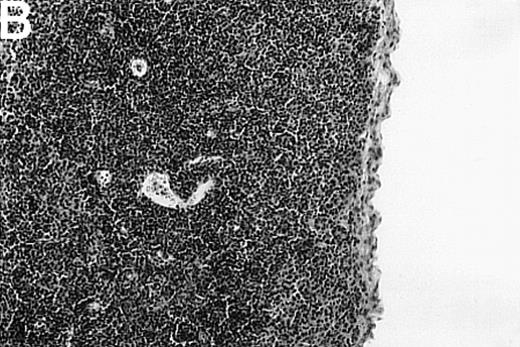

To investigate whether acute or chronic GVHD affects the thymic architecture, an unirradiated P→F1 hybrid model was chosen. After B6→B6D2F1 transplantation, acute GVHD developed, and the thymuses of recipient mice displayed severe morphologic changes (Figure 1). Two weeks after transplantation, the size of the thymus was decreased, and the loss of a regular thymic architecture was apparent with a clear lack of a demarcation between cortex and medulla. In the course of the disease, thymic cellularity progressively decreased and did not recover until the animal's death approximately 4 weeks after transplantation (Figure1D). In contrast, the thymic architecture was not overtly altered during chronic GVHD (DBA/2→B6D2F1). Correspondingly, thymic cellularity was not diminished from this disease when it was analyzed between 1 and 4 weeks after transplantation.

Thymic disease is a consequence of acute but not chronic GVHD.

Acute GVHD was induced by the transfer of 50 × 106parental B6 splenocytes to unirradiated B6D2F1 mice (B), whereas chronic GVHD was induced by the transfer of 80 × 106 parental DBA/2 splenocytes to unirradiated B6D2F1 mice (C). Syngeneically transplanted B6D2F1 mice served as controls (A). Frozen thymic sections (5 μm) were analyzed for histopathology at 2 weeks after transplantation. Magnification ×200. (D) Thymic cellularity as a function of time (total cells per thymus × 10−6) in syngeneically transplanted mice (▵) and in mice with acute (•) and chronic (□) GVHD, respectively. The figure represents combined data (mean ± SEM) of individual mice from at least 8 separate experiments; 20 to 42 mice were analyzed for each group.